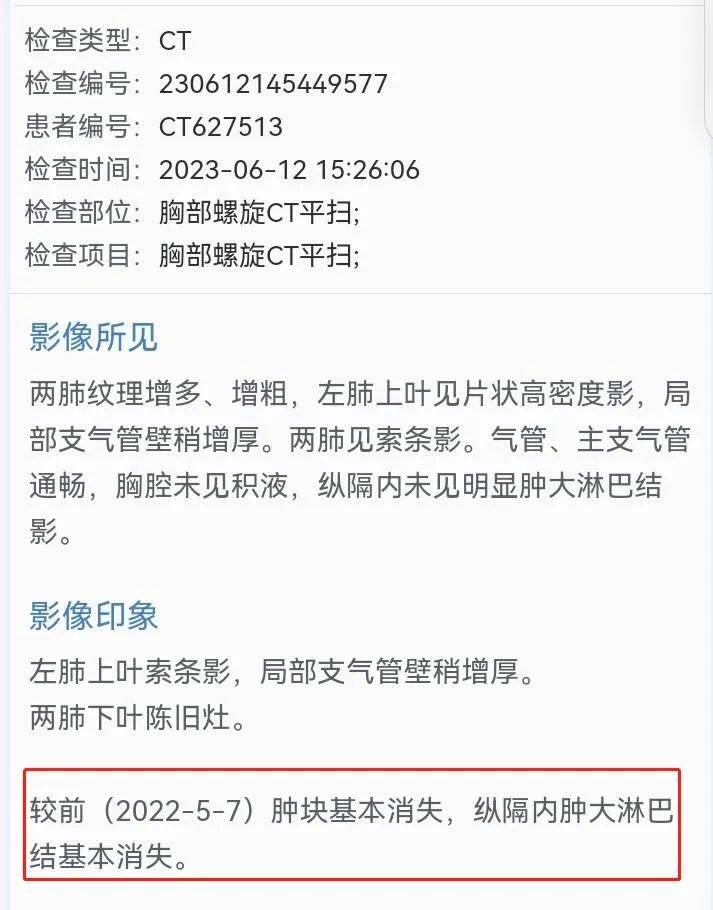

最后一次CT结果:

图片来源:患者提供(点击查看原图)

APP上不少觅友提出疑问:“为什么之前肿瘤还6厘米大,在一个月的治疗后却实现肿块基本消失?”患者家属也对此有过疑惑,甚至担心是“CT乌龙”而选择了换家医院再查CT,最终确定肿块基本消失属实。